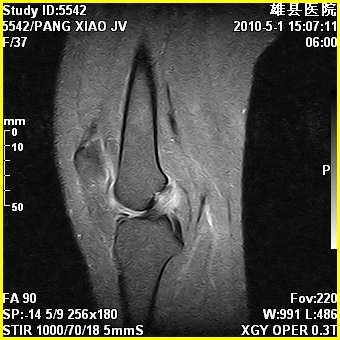

标题: MRI2894:患者右膝关节疼痛两月余,无明显外伤史 [打印本页]

标题: MRI2894:患者右膝关节疼痛两月余,无明显外伤史

右股骨下端前内侧类圆形异常信号,位于干骺端,呈长t1长t2改变,但信号不均,t1图上病灶中心见小片状稍高信号影,t2图上见散在稍低信号影,stir像呈高信号,因病灶较小,缺乏特征性改变,结合患者年龄及部位,考虑嗜酸性肉芽肿可能性大。胫骨关节面下的小囊状异常信号,如果一元论考虑则为嗜酸性肉芽肿,不过发生在这个部位的少见,二元论考虑为邻关节骨囊肿。半月板与前后交叉韧带均未见异常。

右股骨下端前内侧干骺端囊性良性病变,考虑 1内生软骨瘤 2骨囊肿 3肉芽肿。